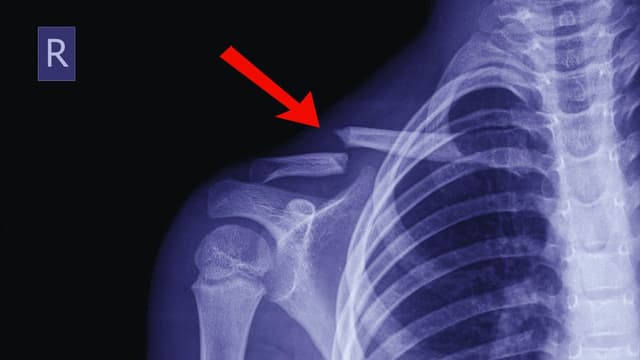

Các phương pháp điều trị trật khớp vai hiệu quả

Trật khớp vai là một trong những chấn thương phổ biến nhất liên quan đến khớp xương, thường xảy ra do va đập mạnh hoặc chấn thương thể thao. Khi vai bị trật, phần đầu xương cánh tay lệch khỏi ổ chảo của xương vai, gây đau đớn và mất khả năng vận động tạm […]

Gãy xương đòn có chơi thể thao được không và những lưu ý

Gãy xương đòn là một bệnh khá phổ biến sau chấn thương, đặc biệt là đối với những người tham gia thể thao hoặc có lối sống năng động. Vậy khi gặp phải tình trạng gãy xương đòn, liệu người bệnh có thể tiếp tục tham gia các hoạt động thể thao hay không? Câu […]